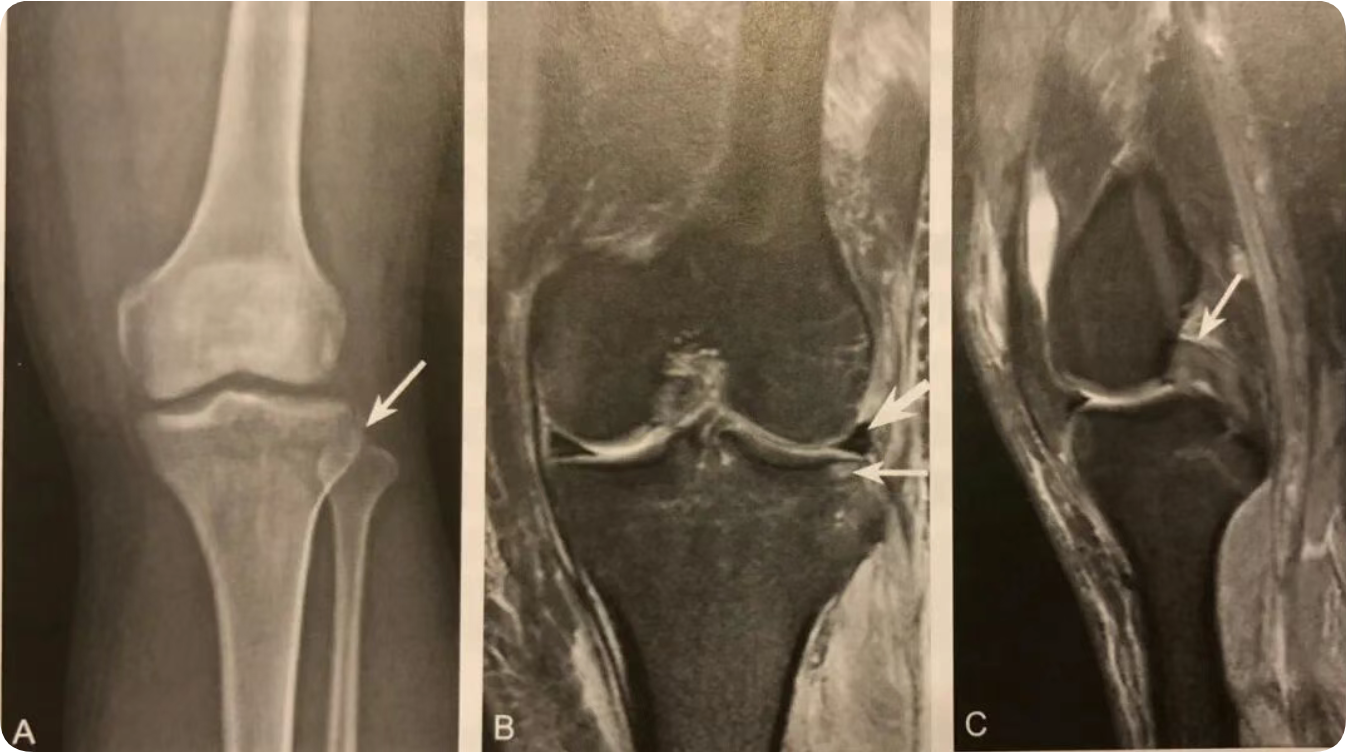

1. 在膝关节 Ⅹ 线前后位片或 CT、MRI 冠状位观察;

2. X 线片或 CT 观察到侧囊征( Segond骨折),应该建议 MRI 检查;

3. Segond 骨折是 PF-ITB 和 ALL 胫骨附着点撕脱骨折的直接征象;

4. Segond 骨折和 ACL 断裂具有高度相关性,但无直接关系;

5. 无 ACL 损伤的 Segond 骨折,MRI 需注意观察其他韧带、半月板及骨质损伤;

6. MRI 注意观察伴发的关节面下对吻性骨挫伤表现。